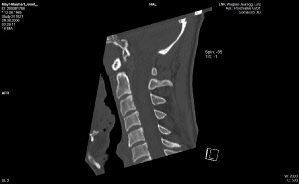

Anbei Daten zur Enthauptung (Heilige Schrift)

Jefferson Fraktur (med. Fachsprache)

Das Bild bekam ich erst vor kurzem

Ist vom 20.11.2017